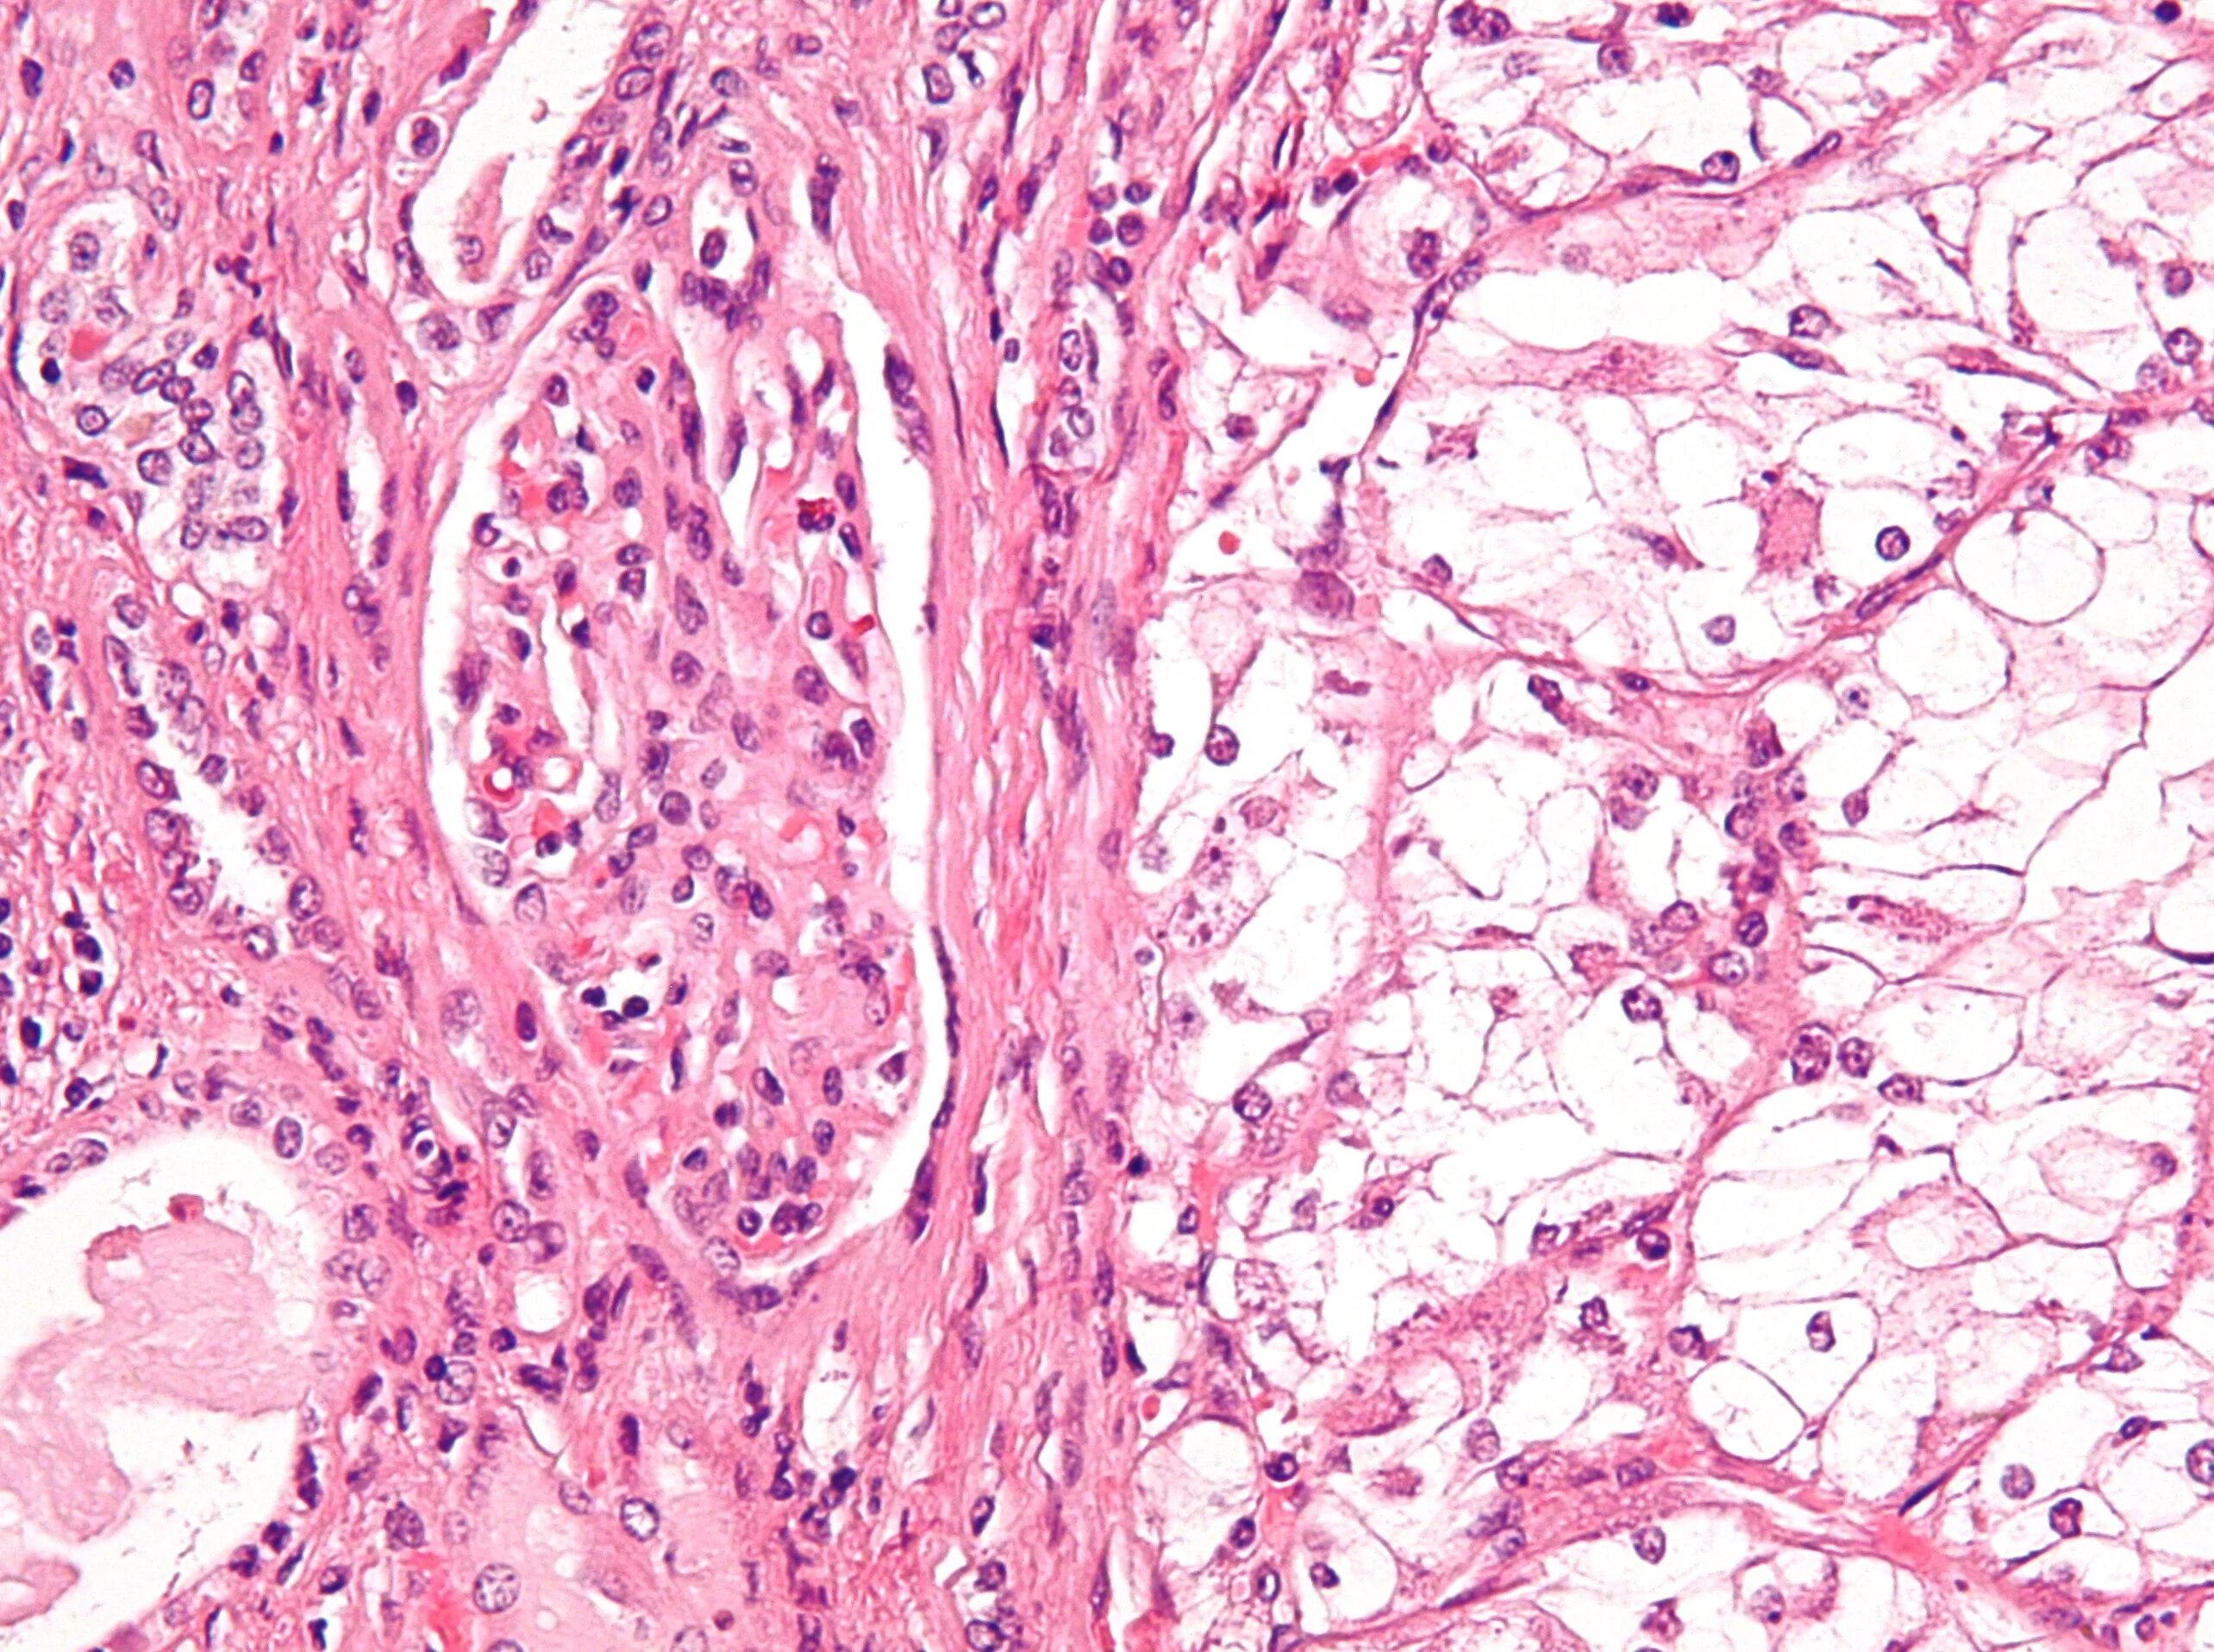

Про гистология